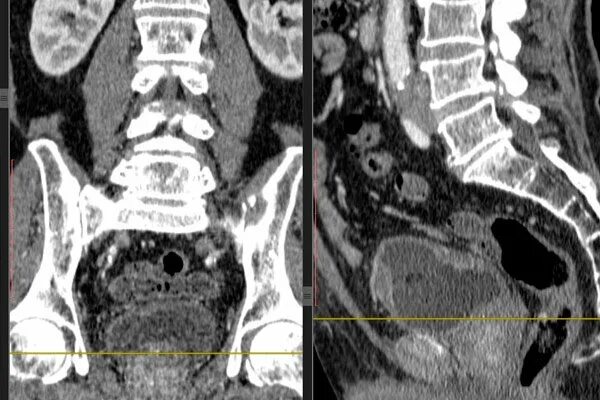

Сколько живут с метастазами в позвоночнике